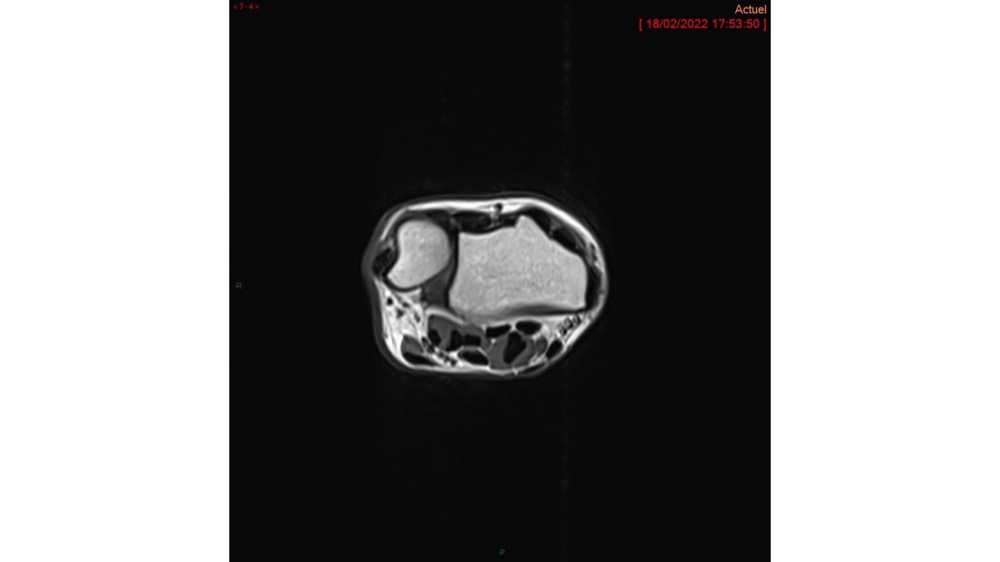

Hussein / Miquel 23/03/2022